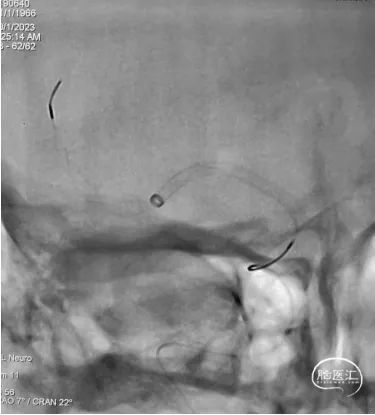

DSA提示:右侧大脑中动脉M1段以远闭塞,右侧大脑前动脉皮层支少量代偿,右侧大脑前动脉A3段血栓影,远端流速可,基底动脉尖端未见显影,考虑急性闭塞。

6F心玮吞川®颅内血栓抽吸导管同轴配合8F心玮天梯®支撑导管在泥鳅导丝导引下放置于右侧颈内动脉眼段。

微导丝配合微导管沿颅内血栓抽吸导管小心通过右侧大脑中动脉血栓段,微导管造影示右侧大脑中动脉远端血流通畅。

确定血栓长度后,以4.0*30mm颅内取栓支架行右侧大脑中动脉取栓配合中间导管抽吸。